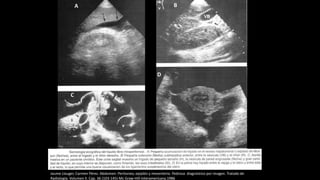

Jaume Llauger, Carmen Pérez. Abdomen: Peritoneo, epiplón y mesenterio. Pedrosa diagnóstico por imagen. Tratado de Radiología. Volumen

II. Cap. 36 (103-145)-Mc Graw-Hill-Interamericana.1986

A B

C

D

A. Teruel López Zurita, B. Díaz Barroso. Ascitis: Qué tenemos que decir los radiólogos. eram2012/S-1549. Sociedad española de radiología médica.

Ascitis maligna: Nodularidad peritoneal por cáncer gástrico